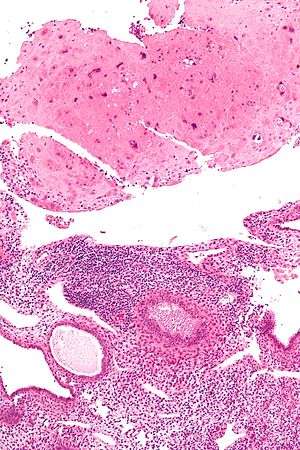

| Micrograph of a placental site nodule (top of image). H&E stain. | |

Typically, they consist of pink (hyaline) material using the standard stain and contain few cells. Bizarre multinucleated cells may be present; however, there is no mitotic activity. The differential diagnosis includes (cervical) squamous cell carcinoma and exaggerated placental site.